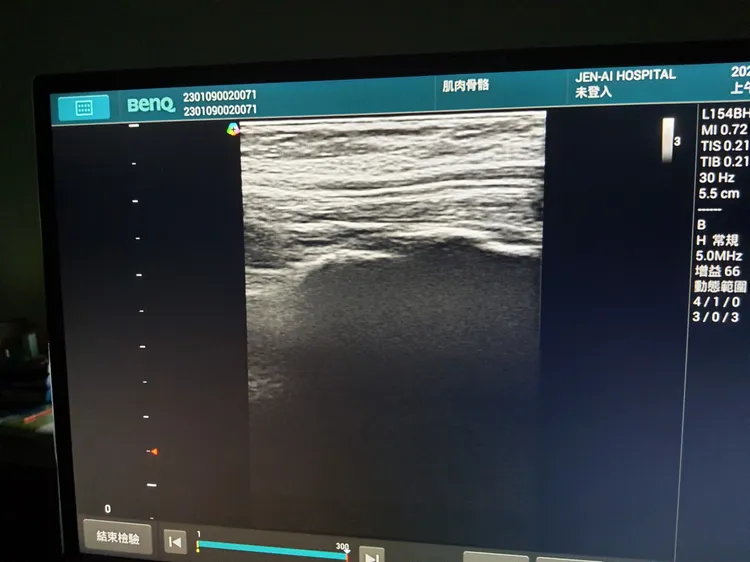

醫用超音波可提供更好影像解析度,近年來廣泛地使用在脊椎神經與周邊神經等的止痛與增生治療。大里仁愛醫院提供

張育銘指出,現今影像技術進步,醫用超音波可以提供更好的影像解析度,因此近年來被廣泛地使用在脊椎神經與周邊神經等的止痛與增生治療。因為醫師可以看得更清楚,所以可以避免傷害到重要的神經、血管與組織等,並且精準地將藥物給注射到目標處,且在門診就能夠馬上檢查、診斷然後治療。

張育銘醫師說,透過超音波導引藥物注射改善疼痛成功率現已達9成5左右,病人可迅速得到緩解減少使用止痛藥物。大里仁愛醫院提供